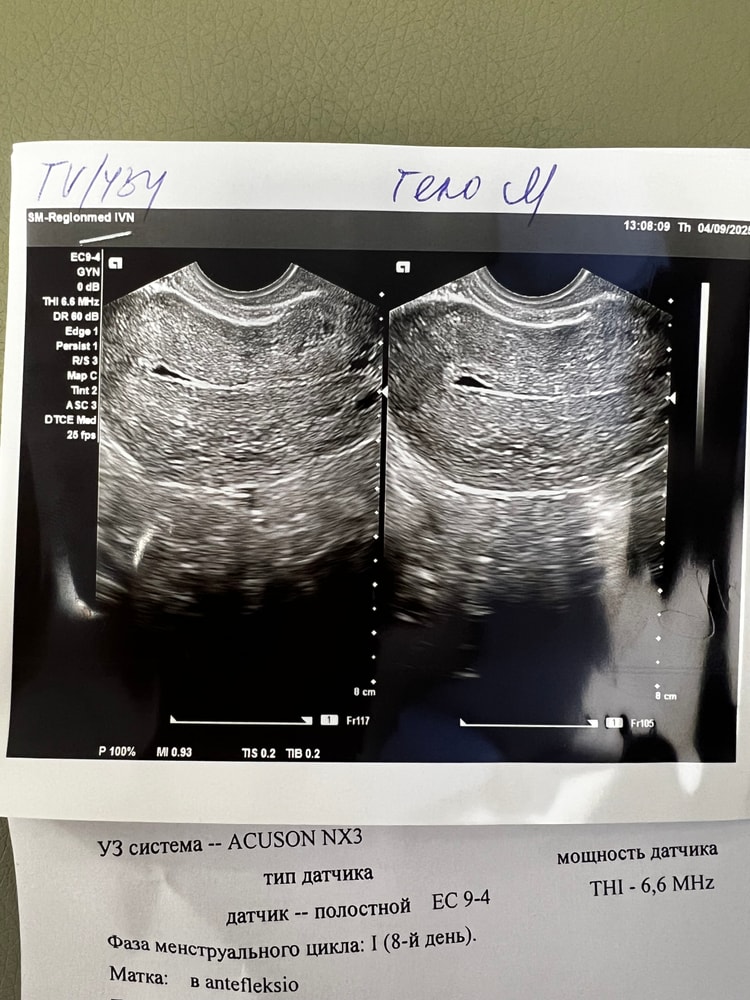

Могу сказать по своему опыту - после ЗБ была гематометра, у меня ее было видно сразу, и она не проходит безболезненно. Могла бы предположить, что у вас могут быть остатки плода, но опять же по своему опыту - остатки видно на любой день цикла. Судя по фото ниже, у меня через несколько месяцев после ЗБ на узи нашли что-то похожее - под вопросом ставили эндометриодную гетеротопию. Большего предположить не могу, к сожалению, лучше сходить к врачу, гематометра и остатки плода - это довольно опасно.

случится чудо, нашла бумажки по УЗИ - делала его через 3 месяца после вакуума и через 2 месяца после гистероскопии (удаляли остатки плода) - на 6 день цикла этого не было, а вот на 24 дц как раз под вопросом поставили вот эту эндометриоидную гетеротопию миометрия. Больше я на УЗИ не ходила. Сходила к врачу, она сказала, что это не страшно, это лечится установкой спирали вроде как, но я на тот момент уже была близка к повторному планированию Б, поэтому она сказала, что ничего делать не нужно. Собственно, потом я уже забеременела. единственное, добавлю - еще это может быть полип (после вакуума их развитие очень распространено), но вроде как полипы врачи на УЗИ видят сразу, если бы это был он , то вам бы сказали. Но лучше наверное еще раз сделать УЗИ в динамике и сходить к врачу.

Изображение Изображение